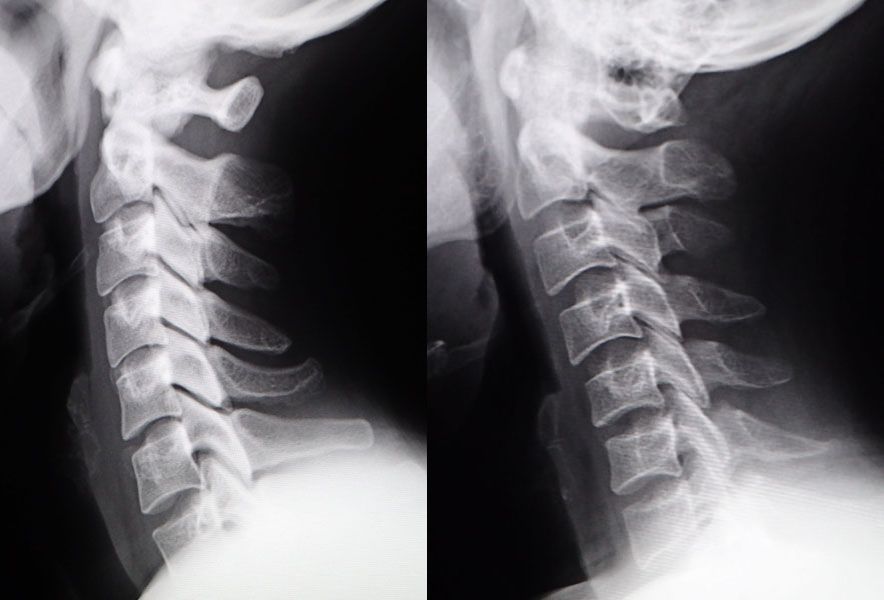

人間の背骨はもともと前後の彎曲を持っており、頸椎には前方に凸の彎曲(前弯)があります(左図)。

ところがパソコン面に集中するあまり頭が前方に移動すると、頸椎は前弯を失ってまっすぐになったり、後方に凸の彎曲を有するようになります(右図)。

この状態がストレートネックで、首の後ろの筋肉が緊張して肩こりや痛みの原因になります。